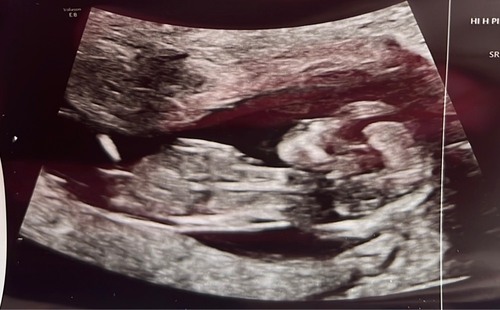

Hee allemaal, zojuist een echo gehad op 13+4. Ik weet niet zo goed of dit een goede foto is voor de nub.. iemand die een gokje kan wagen op basis hiervan? 🥰💖🩵

Reactie op RW90

Hee allemaal, zojuist een echo gehad op 13+4. Ik weet niet zo goed of dit e ...

Meisje

Ik denk een meisje